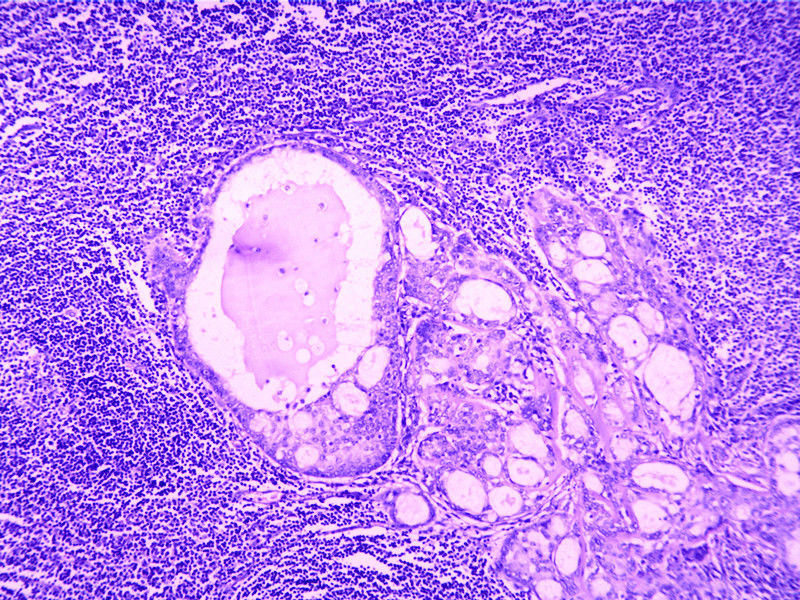

要想Hold住这个肿物的病理诊断,需要了解:

需要鉴别的肿瘤:

(1)皮脂腺淋巴腺瘤

(2)伴有淋巴组织间质的皮脂腺癌(皮脂腺淋巴腺癌)

(3)良性淋巴上皮病

(4)粘膜相关淋巴组织淋巴瘤(MALT淋巴瘤)

(5)转移性粘液表皮样癌